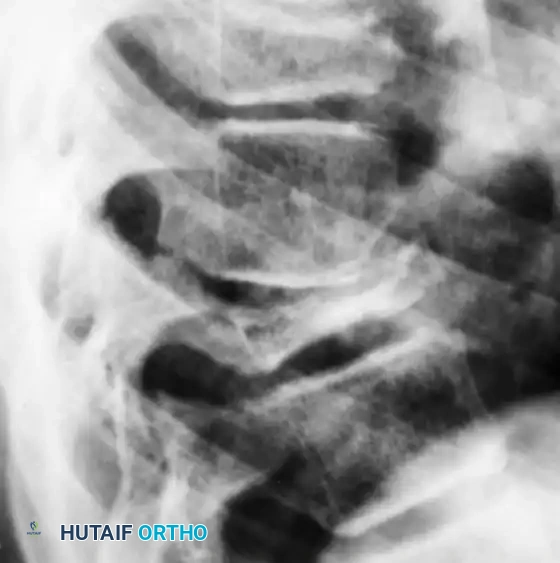

Eosinophilic granuloma of the vertebral body. Severe compression of the body produces the classic radiographic changes of vertebra plana. The adjacent disc spaces remain intact.

* Spine: LCH is the most common cause of vertebra plana (severe, uniform flattening of the vertebral body) in children. The intervertebral disc spaces are classically preserved, differentiating it from infectious spondylodiscitis.

- Long Bones: Diaphyseal lesions often exhibit an aggressive, permeative pattern of bone destruction with robust, lamellated periosteal